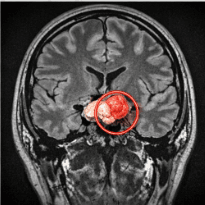

실제 뇌하수체 선종 보험금 분쟁 사례를 하나 말씀드리겠습니다. 이분은 심한 두통과 시야 장애로 병원을 찾았다가 뇌하수체 종양을 발견하고 수술을 받으셨습니다. 병원에서는 D35.2 진단서를 끊어주었고, 보험사는 당연히 “소액암에 해당한다”며 300만 원의 지급 결정을 통보했습니다.

하지만 저는 포기하지 않았습니다. 환자분의 병리 보고서와 MRI 영상을 며칠 밤낮으로 분석했습니다. 그 결과, 종양이 이미 왼쪽 해면정맥동을 깊숙이 파고든 상태였고(침윤), Ki-67 지수 또한 일반적인 양성 범위를 넘어서 있었습니다.

- 의무기록 사본 확보: 진단서뿐만 아니라 ‘병리 보고서’와 ‘수술 기록지’, ‘MRI 판독지’를 반드시 챙기세요.

- 의학적 증거 추출: 종양의 침윤 여부, 증식 지수(Ki-67), 주변 조직 압박 정도를 전문가와 함께 분석해야 합니다.